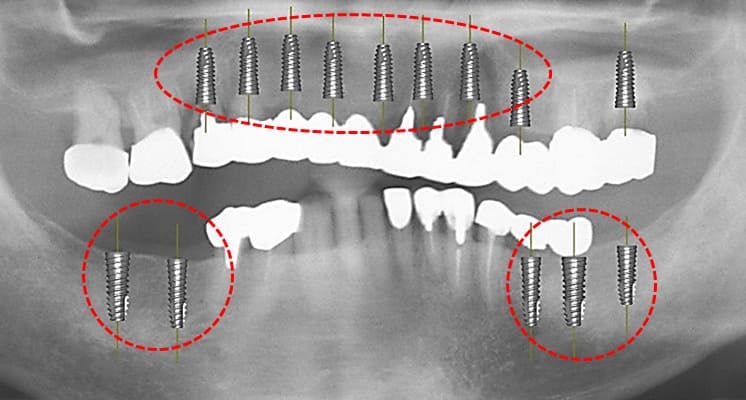

上顎前歯部と小臼歯部の温存不可能な残根を抜歯して1か月ほど待機して歯肉が抜歯窩を完全に閉鎖した状態でCTと口腔内の印象を取り最終補綴の予想WAX UPを1行いサージカルガイドを作成した。その後、上顎にインプラント8本を埋入した。

上顎にインプラント8本を埋入した術後のパノラマXP所見:上顎骨に対するインプラントの長さに関しては12mm-10mmが適切であり前歯部では12mmを小臼歯部では10mmを選択している。また左下のブリッジに関しては温存できなかった第2大臼歯が抜去されている。

上顎のインプラント埋入後約1か月で、両側下顎臼歯部にインプラント埋入を行った。左下のインプラント埋入では小規模の骨増生を伴うインプラント埋入を行った。

両側下顎臼歯部に対してのインプラントについては8mmから10mmが選択されるが骨量が十分あったことから10mmを選択して埋入した。左側の小臼歯部では水平的骨が若干、不足しているためドリリング時に採取された自家骨を骨増生として利用した。

上顎前歯部と両側小臼歯部はインプラント補綴を行い、両側の大臼歯部についても根管治療からやり直して咬合平面を改善すべく補綴を行った。下顎の両側臼歯部に関してもインプラント補綴を行い小臼歯部では根管治療からクラウンによる補綴を行った。左上7番に関しては当初インプラント補綴を行う予定であったがサイナスリフトを伴う治療になることと第一大臼歯までで十分噛めることから埋入せずに経過を見ている。